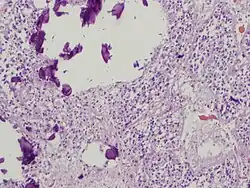

Microanatomy

The pineal body in humans consists of a lobular parenchyma of pinealocytes surrounded by connective tissue spaces. The gland's surface is covered by a pial capsule.

The pineal gland consists mainly of pinealocytes, but four other cell types have been identified. As it is quite cellular (in relation to the cortex and white matter), it may be mistaken for a neoplasm.[18]